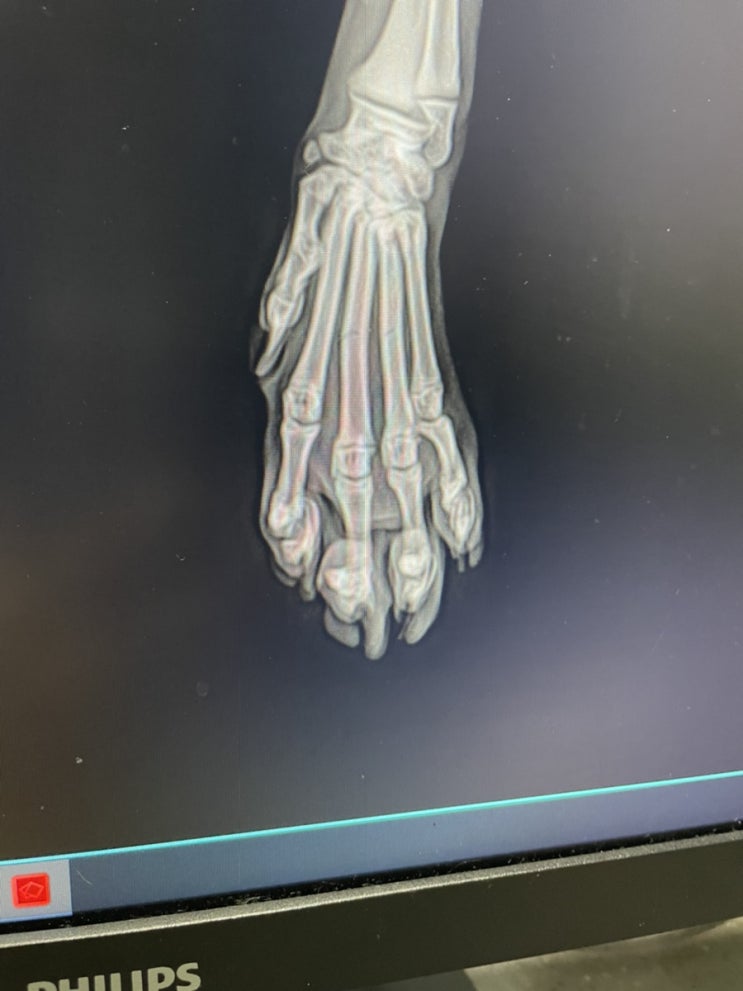

드라마틱한 하루였다. 다 골절 되고 남은 발가락 뼈 몇개로 결승선까지 한발한발 딛으며 크게 한 숨 들이마...